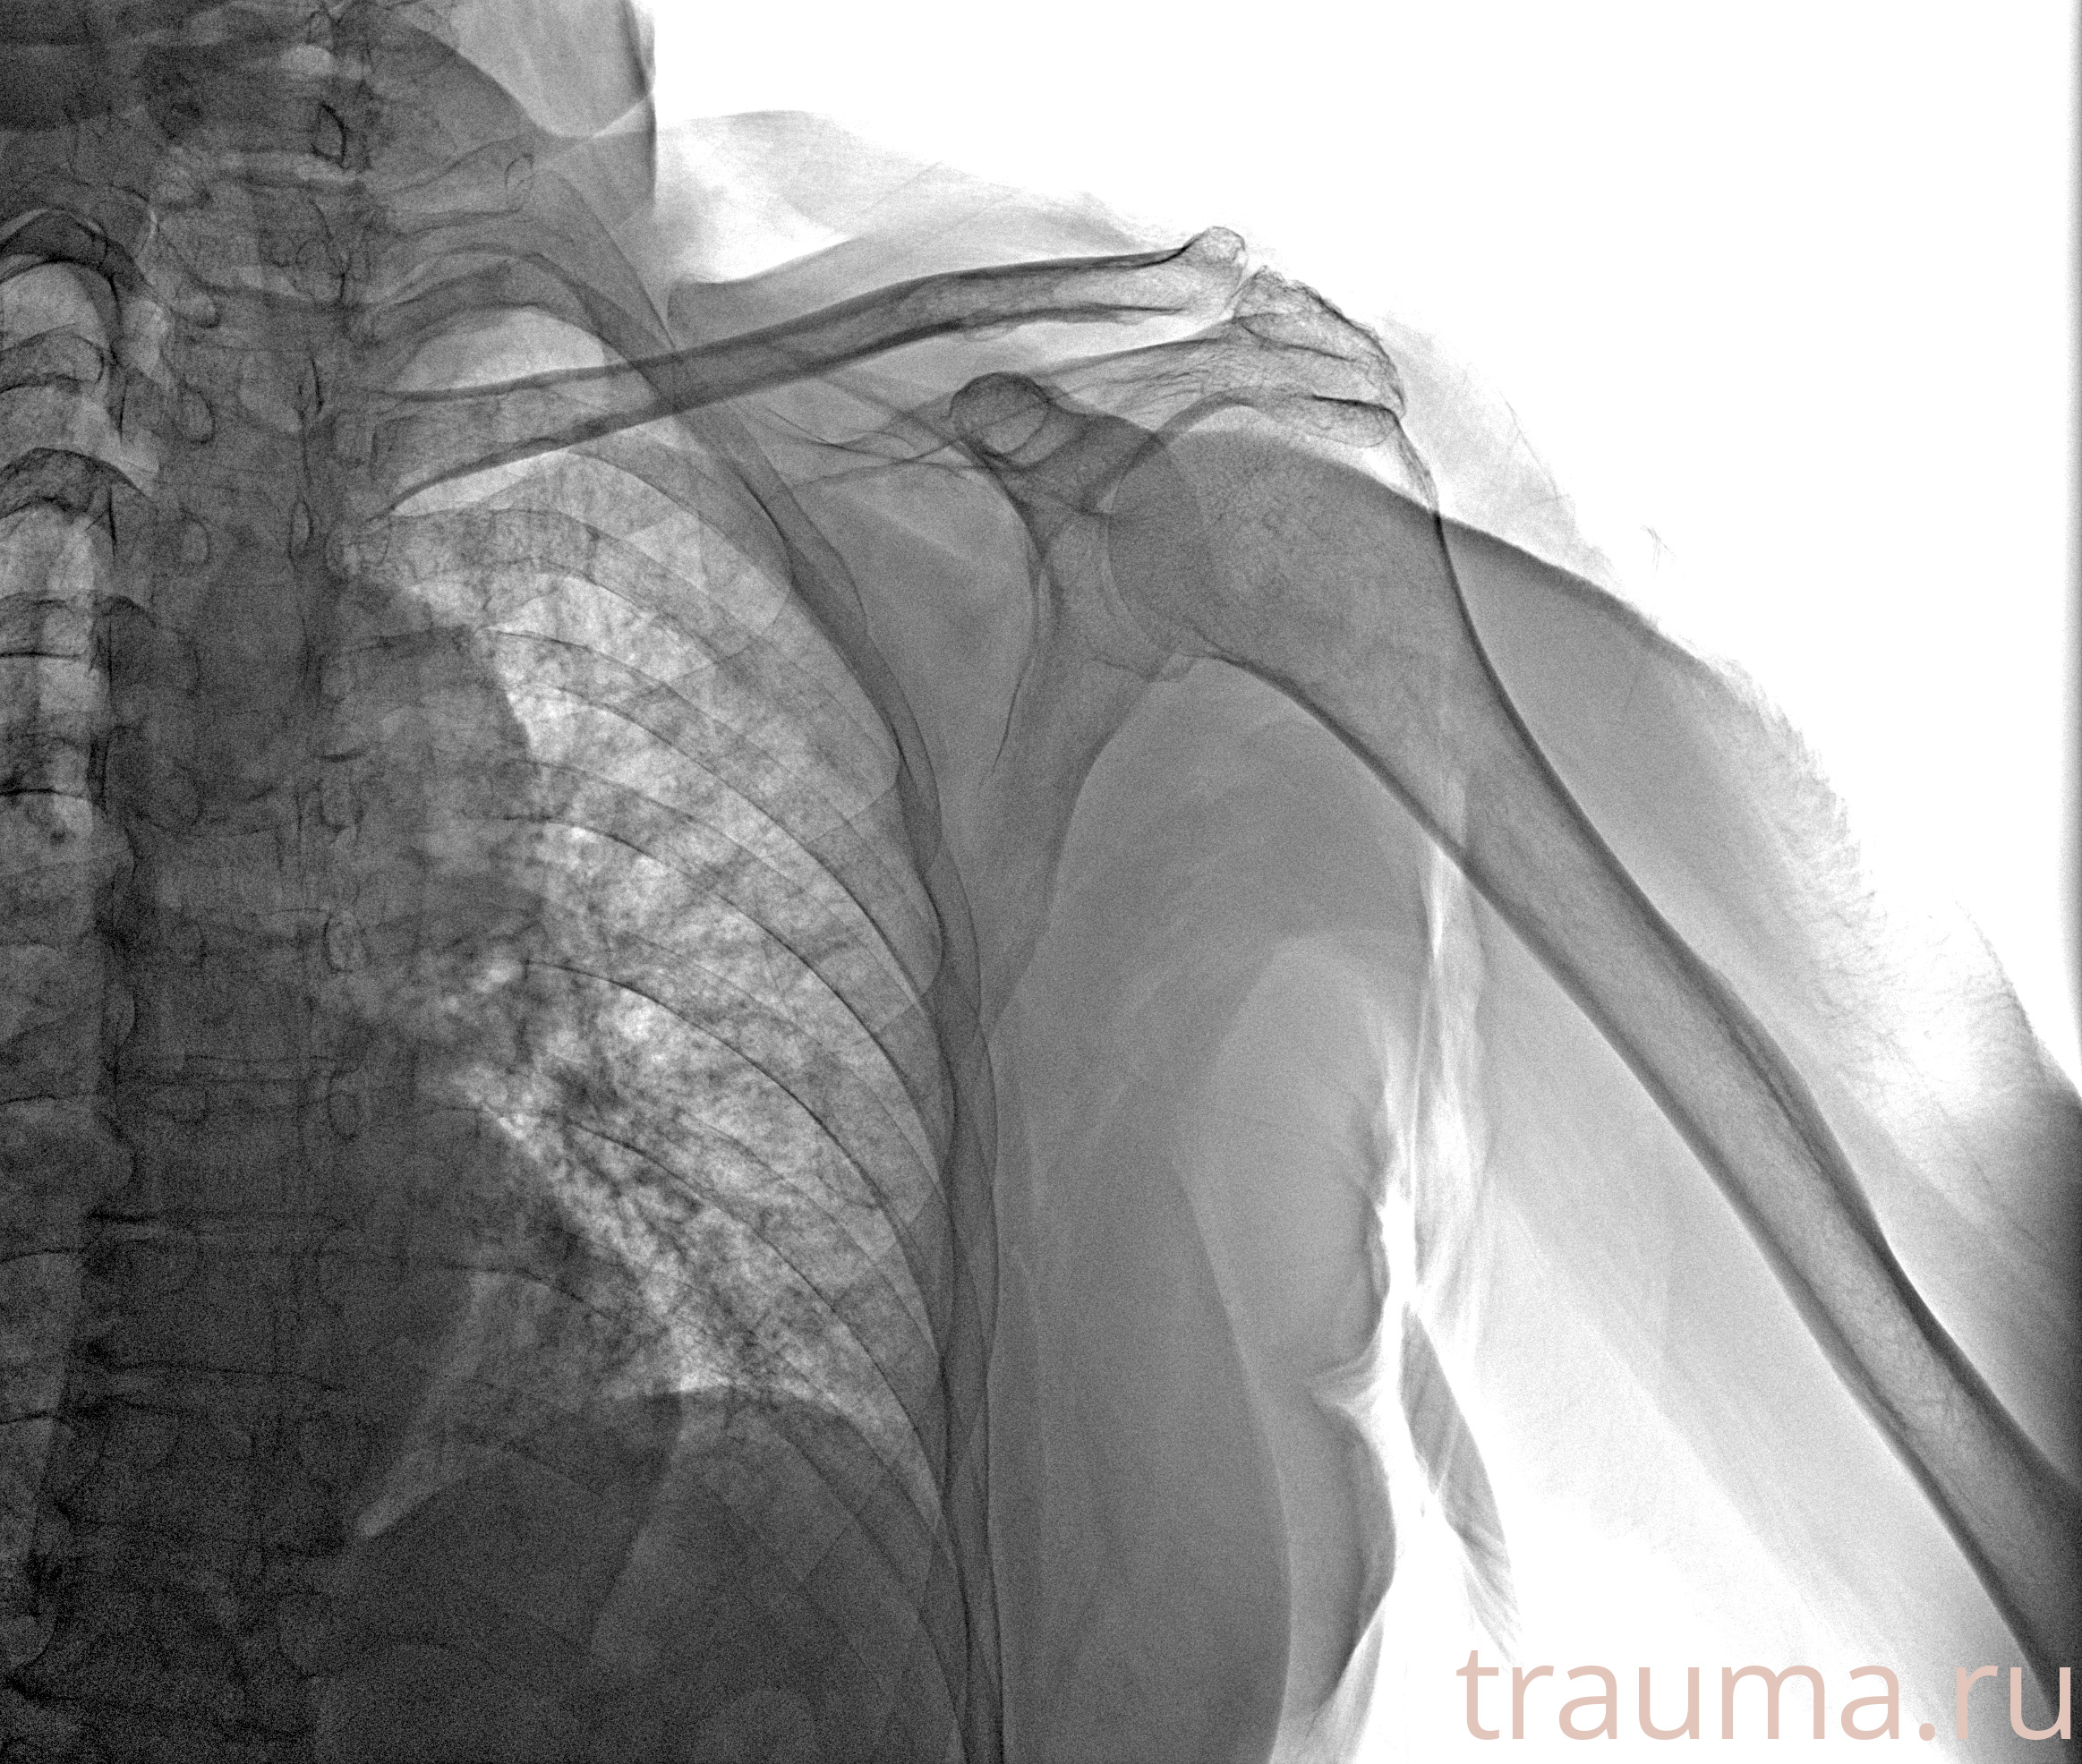

Рентген на дому: по вашему адресу приезжает врач-рентгенолог, травматолог-ортопед с мобильным рентгеновским аппаратом, проводит диагностику травмы или заболевания, делает необходимые рентгенограммы, дает рекомендации по дальнейшему лечению. Получить качественные снимки в домашних условиях возможно благодаря уникальной методике, разработанной МосРентген Центром для института  Склифосовского